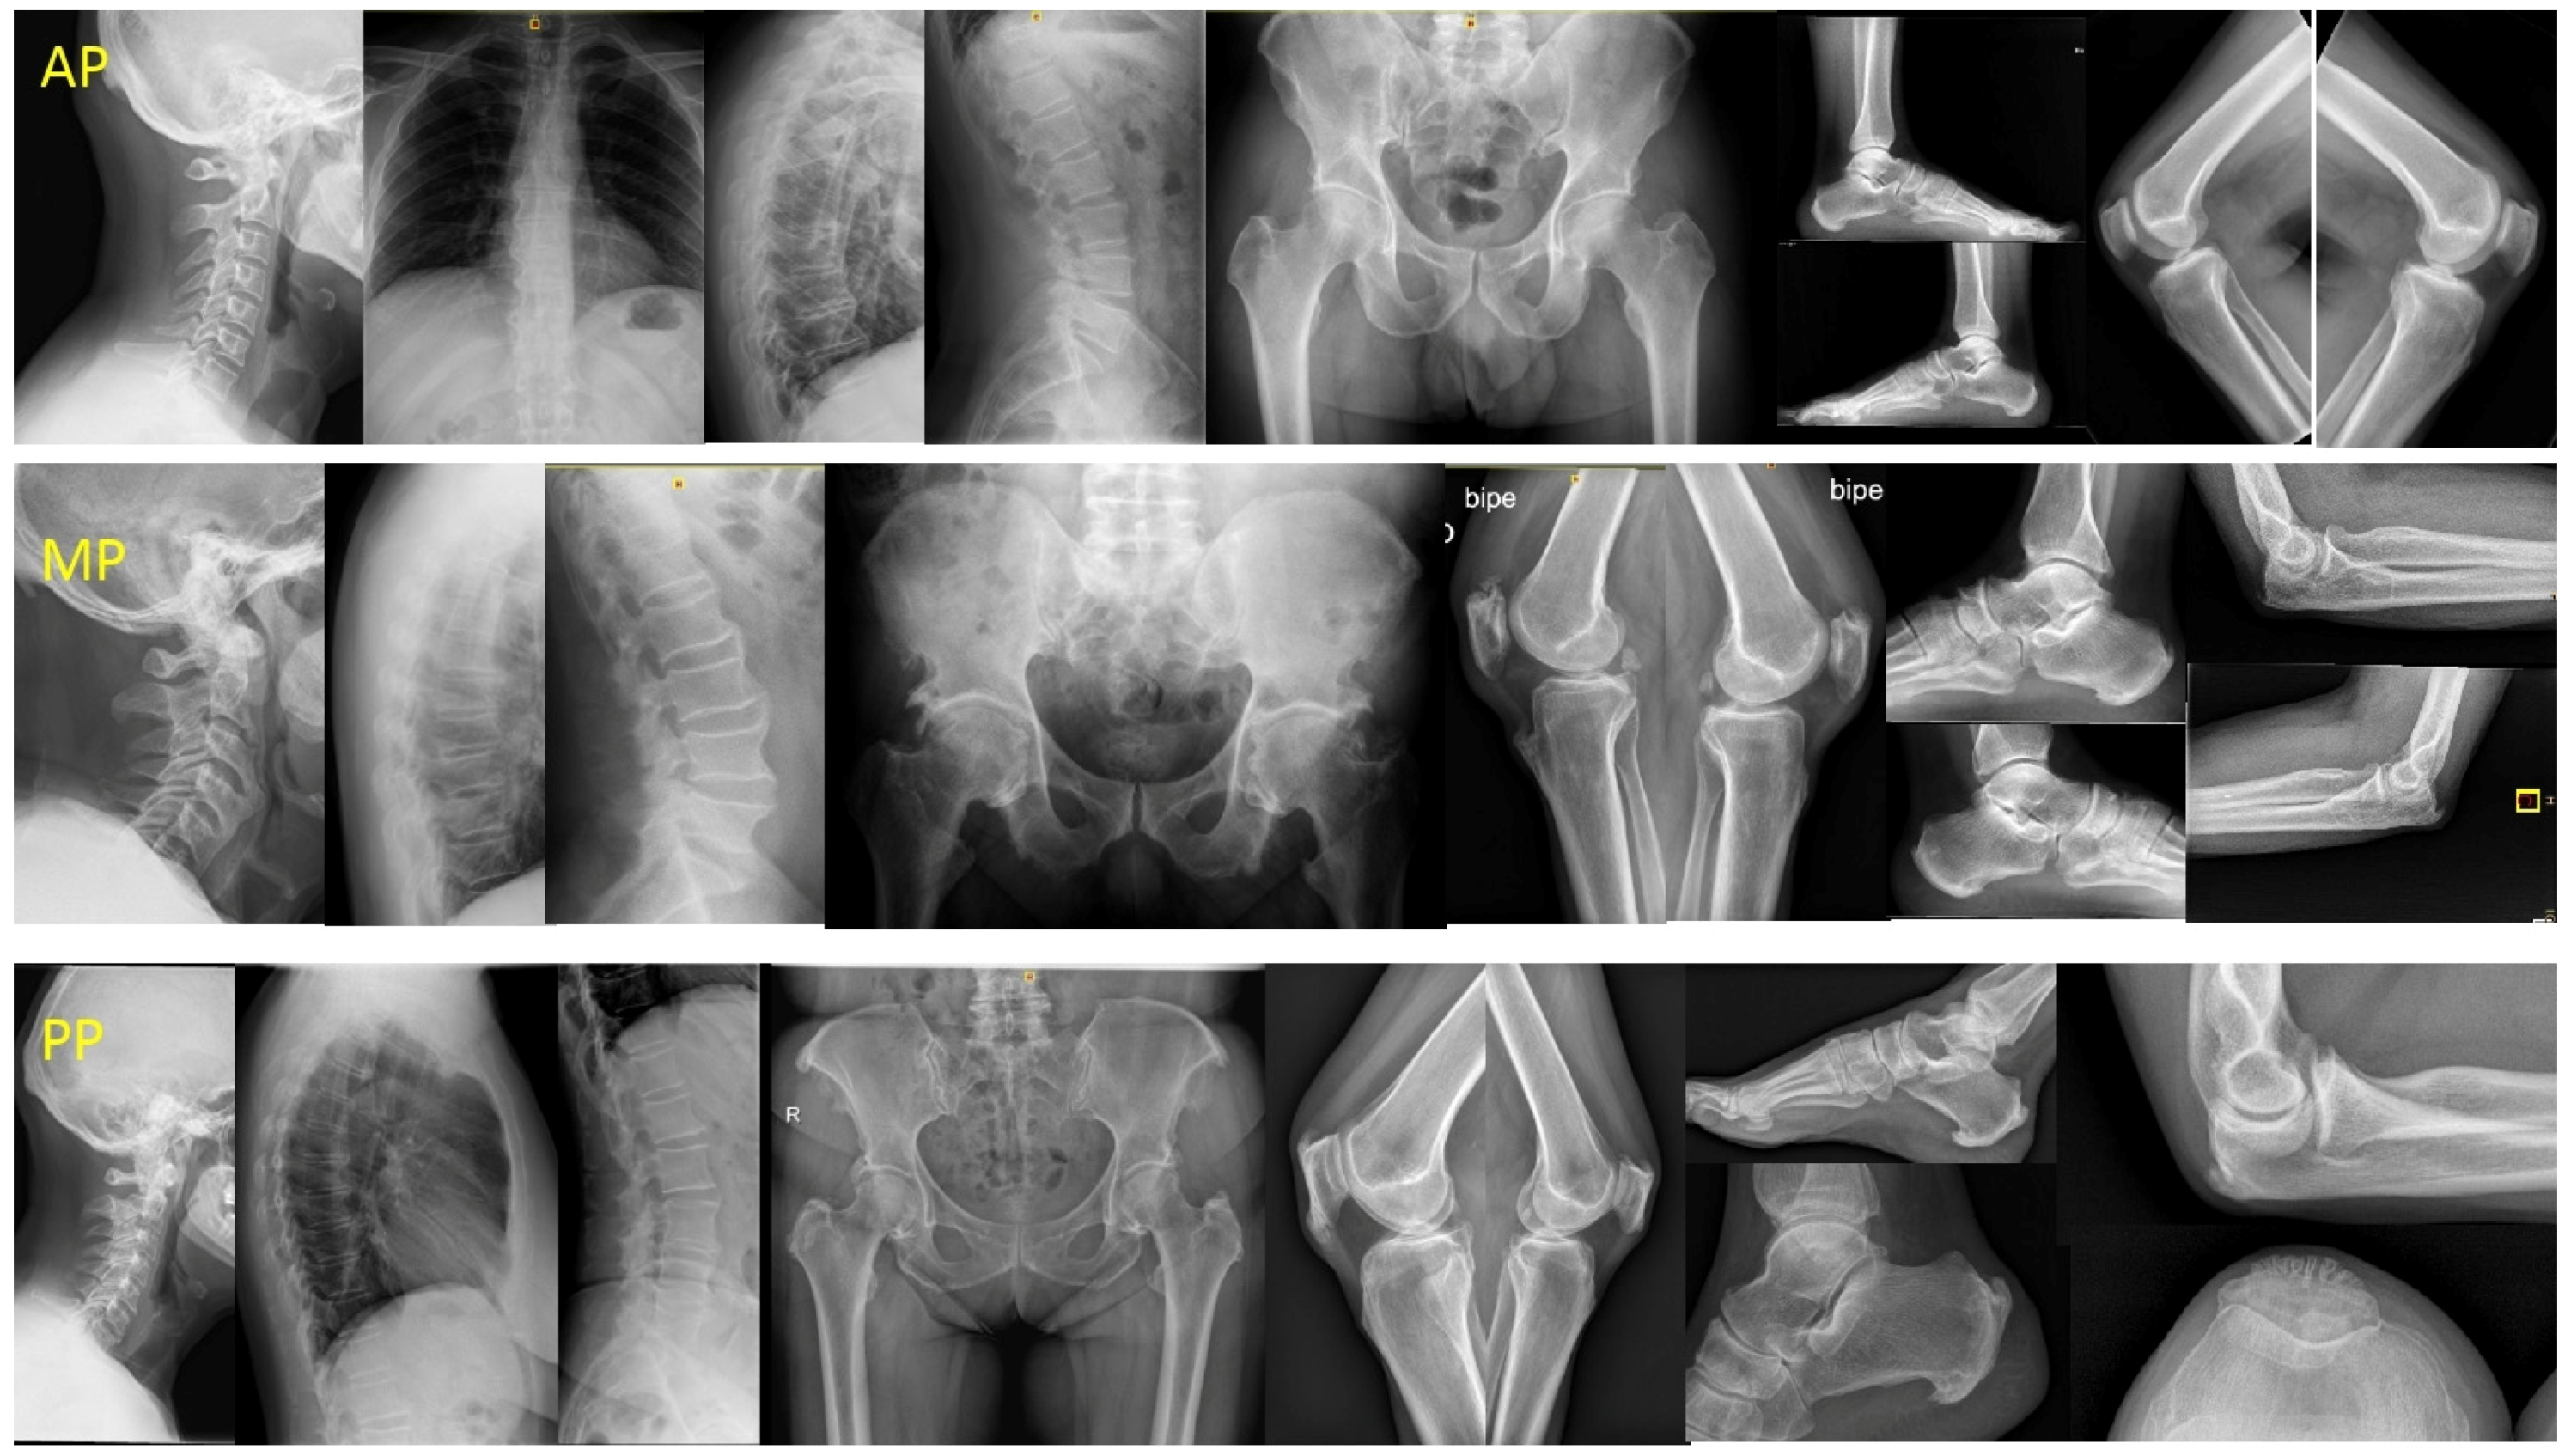

Based on previous observations, we proposed three clinical-radiological patterns: (a) peripheral pattern (PP) for patients who did not fulfil the Resnick criteria but who presented ≥3 peripheral enthesopathies (probable or possible Utsinger categories) with or without vertebral spine manifestations; (b) axial pattern (AP) for patients who met the Resnick criteria but who presented <3 peripheral enthesopathies; and (c) mixed pattern (MP) for patients who met the Resnick criteria but who presented ≥3 peripheral enthesopathies (Figure 1).

Figure 1.

DISH patterns. Legend: AP: male 54 years, 10 years evolution. DISH signs in TL spine and only one enthesophyte (K) with no hip involvement. MP: male 70 years, 20 years evolution. Ankylosed column. Severe coxopathy. More than three peripheral enthesophytes (E, K, A). PP: female 68 years, 18 years evolution. No spine involvement, suspicion in CC. Almost all entheses affected (E, MT, K, A, C). DISH: Diffuse idiopathic skeletal hyperostosis; AP: axial pattern; MP: mixed pattern; PP: peripheral pattern; TL: thoracolumbar; E: elbows; MT: major trochanter; K: knees; A: Achilles; C: calcaneus; CC: cervical spine.